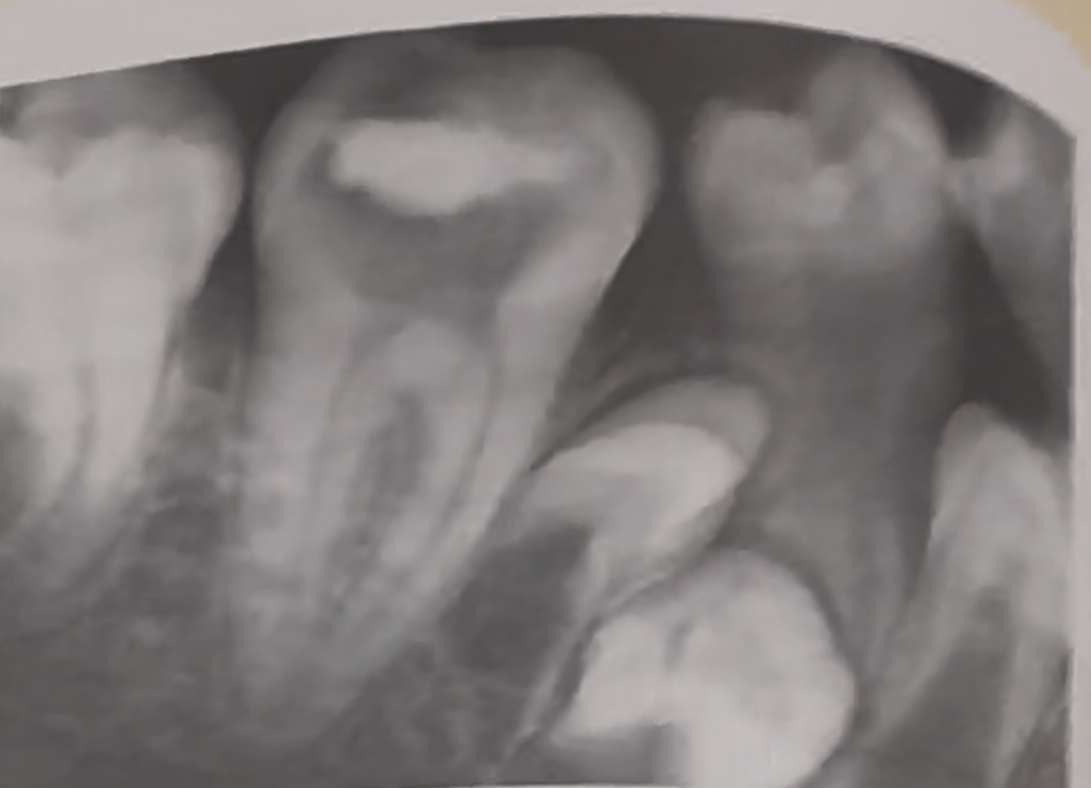

Impaction in mixed dentition |

unerupted supernumerary teeth

Impacted third molar |